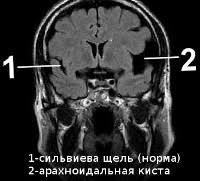

- Магнитно-резонансную томографию (МРТ) — позволяет получить детальные изображения мягких тканей мозга и обнаружить наличие кисты.

- Компьютерную томографию (КТ) — помогает определить особенности структуры и образования в мозге.